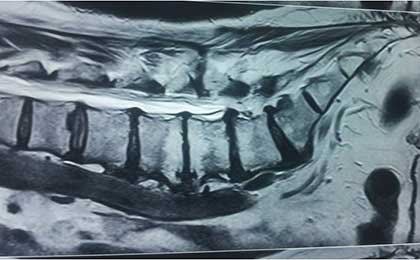

LUMBAR SEQ DISC

lumbar discectomy post op 2

lumbar Disc 2

Lumbar Disc Postop 1